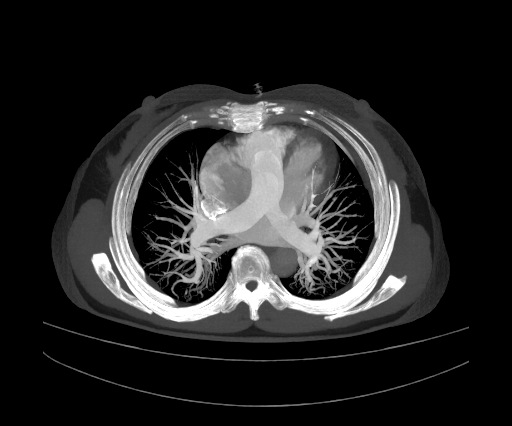

非常见肺部疾病可解释的严重低氧血症、D二聚体升高,需要警惕肺栓塞。李藻颖医生立即与患者家属沟通,告知病情并建议完善肺动脉CTA。在征得患者家属同意后,立即联系放射科完善肺动脉CTA,并予低分子肝素预防抗凝。

过程虽然惊险,但血栓总算是“化”掉了,埋在患者肺动脉的“定时炸弹”被成功拆除。

住院期间廖阿姨生命体征相对平稳,未出现明显右心衰表现,评估为低危组,故给予抗凝治疗。